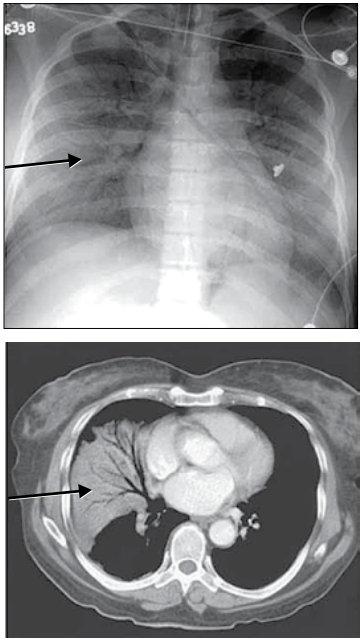

Analise as imagens.

Qual é o achado radiológico indicado pelas setas nessas imagens?

Analise as imagens.

Qual é o achado radiológico indicado pelas setas nessas imagens?